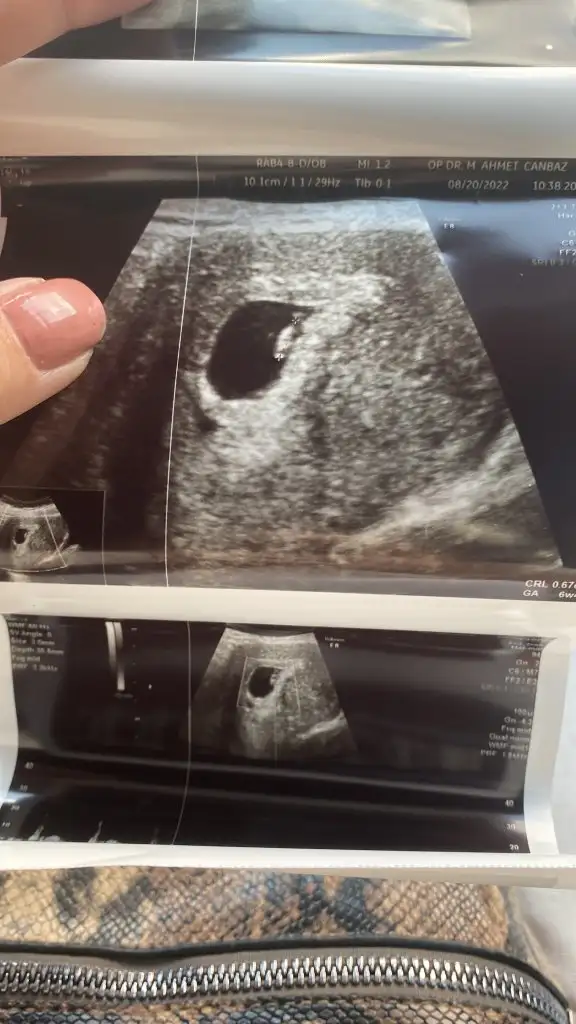

Lütfen lütfen bana da yorum yaparmisiniz biri 6 haftalik digeri 11 haftalik🙏🙏🙏